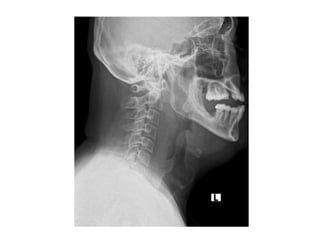

• Contrast-enhanced CT:- gold-standard imaging modality

• Due to potential communication of the visceral, retropharyngeal, danger

and prevertebral spaces with the mediastinum it is imperative to include

the mediastinum in the CT scan field.

• Abscesses:- characteristic rim enhancement on CT imaging

• Cellulitis:- fluid and fat stranding in the subcutaneous tissues and along

fascial planes

• Myositis:- enlargement and hyperenhancement of the adjacent

musculature

• Ultrasound:- whether an abscess has sufficiently liquified to be drained,

• Orthopantomogram:- infection of dental origin